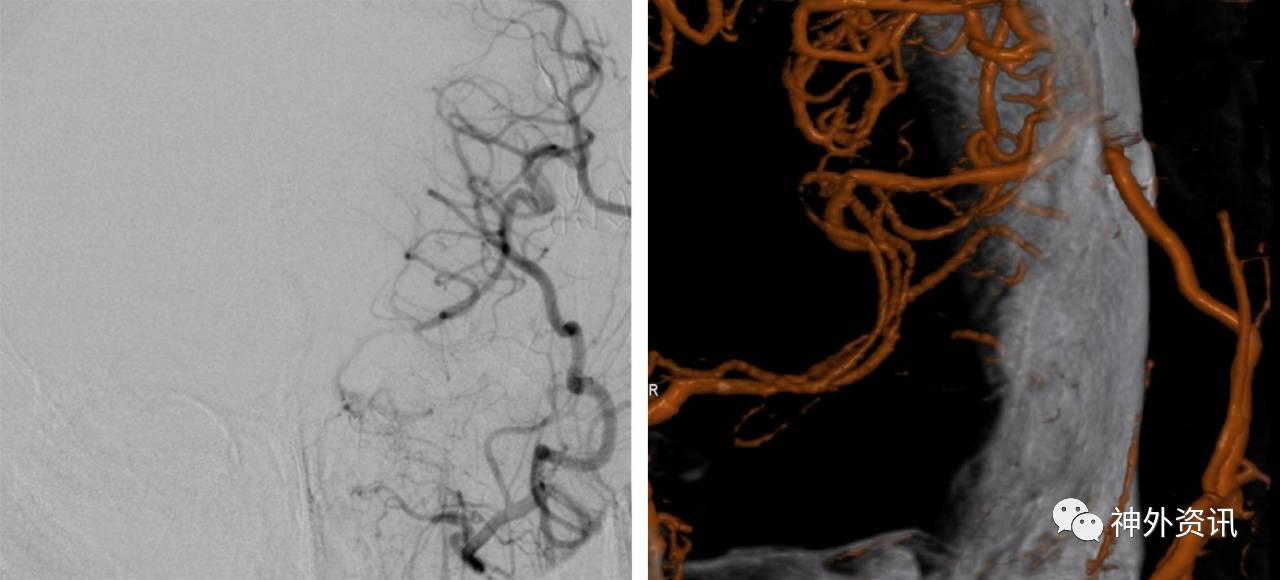

图12:患者出院后定期随诊复查导管造影或者CTA来评价搭桥的通畅性。此例行左侧STA-MCA搭桥的患者其桥血管保持畅通(右图为三维重建影像)。